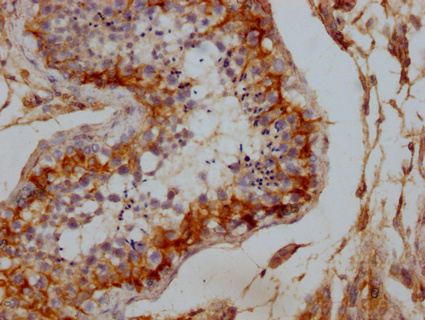

• IHC image of CSB-PA006938LA01HU diluted at 1:100 and staining in paraffin-embedded human testis tissue performed on a Leica BondTM system. After dewaxing and hydration, antigen retrieval was mediated by high pressure in a citrate buffer (pH 6.0). Section was blocked with 10% normal goat serum 30min at RT. Then primary antibody (1% BSA) was incubated at 4°C overnight. The primary is detected by a Goat anti-rabbit IgG labeled by HRP and visualized using 0.05% DAB.